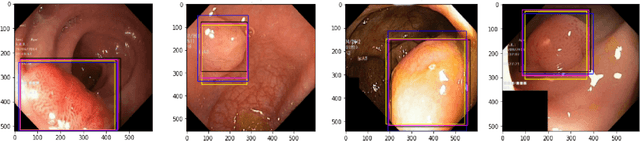

Abstract:Knowledge distillation (KD) is an effective model compression technique where a compact student network is taught to mimic the behavior of a complex and highly trained teacher network. In contrast, Mutual Learning (ML) provides an alternative strategy where multiple simple student networks benefit from sharing knowledge, even in the absence of a powerful but static teacher network. Motivated by these findings, we propose a single-teacher, multi-student framework that leverages both KD and ML to achieve better performance. Furthermore, an online distillation strategy is utilized to train the teacher and students simultaneously. To evaluate the performance of the proposed approach, extensive experiments were conducted using three different versions of teacher-student networks on benchmark biomedical classification (MSI vs. MSS) and object detection (Polyp Detection) tasks. Ensemble of student networks trained in the proposed manner achieved better results than the ensemble of students trained using KD or ML individually, establishing the benefit of augmenting knowledge transfer from teacher to students with peer-to-peer learning between students.